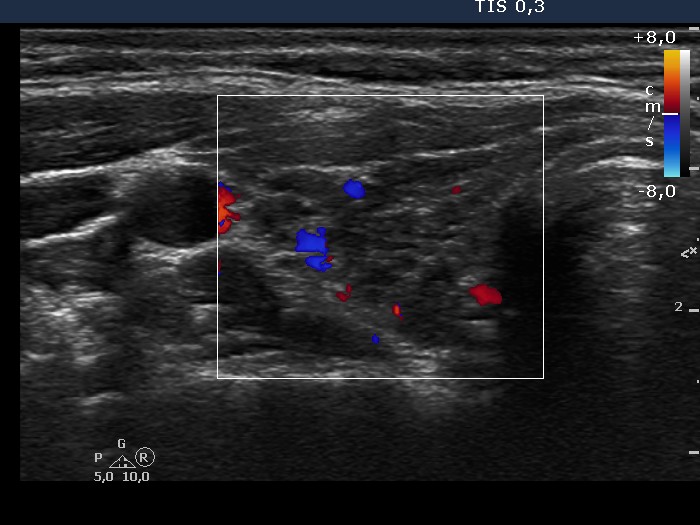

Chronic lymphocytic thyroiditis - Case 36. |

Clinical data: a 35-year-old woman with hypothyroidism replaced with 100 ug levo-tiroxin was referred for evaluation of thyroid nodules.

Ultrasonography: there were several circumscribed areas which in fact did not fit nodules. These are active foci of autoimmune thyroiditis.

Cytological report: benign Hashimoto's thyroiditis.